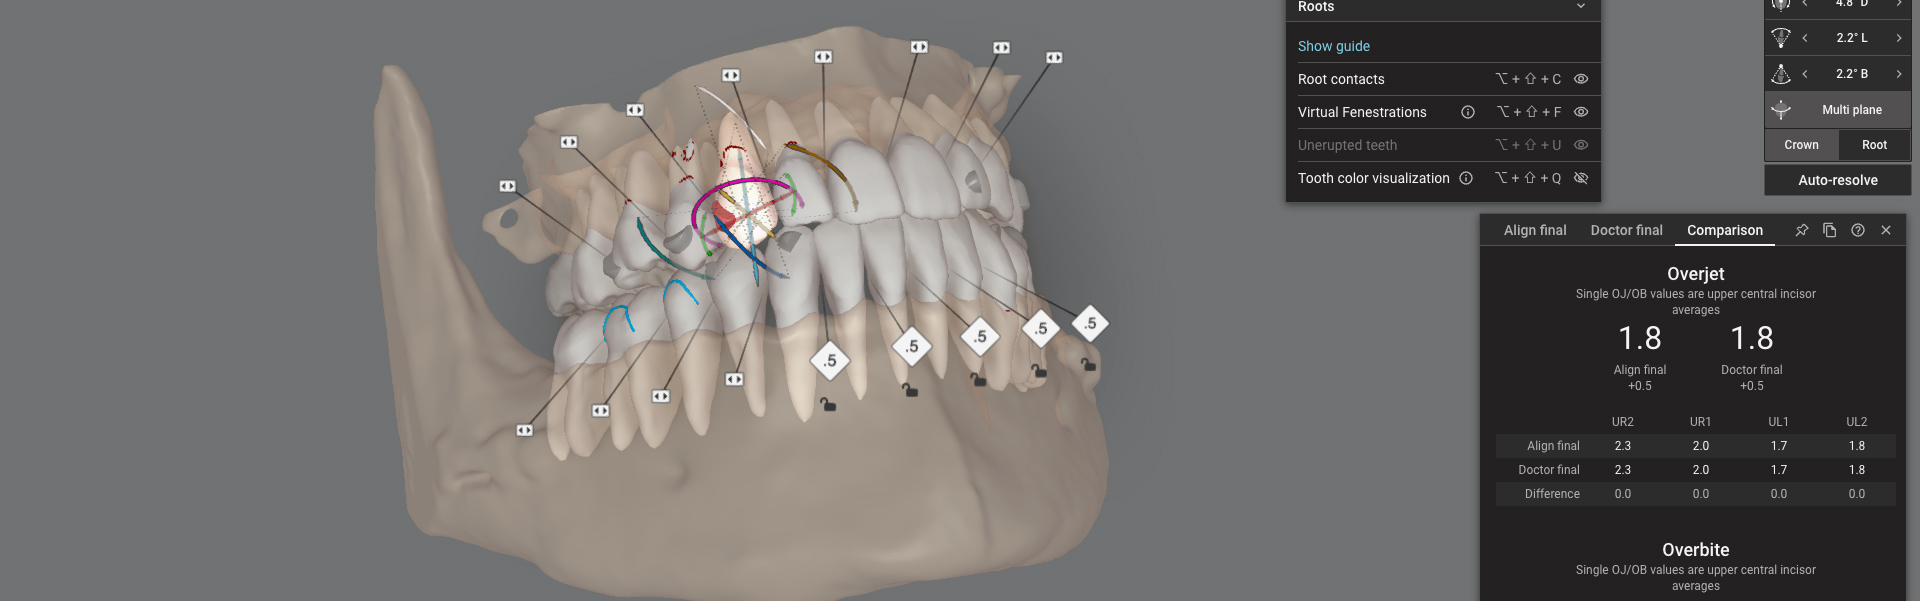

3D Scan and Detailed Explanation

We’ll take a 3D scan of your teeth using our iTero scanner. This allows us to give you a detailed view of your current alignment and provide a visual explanation of the proposed treatment. This advanced technology makes it easier for you to see what to expect from your orthodontic journey.

3D simulation , Video Simulation

We will share your 3D simulation called ClinCheck with you. We now have the technology to simulate your smile not only from your picture but also to create a video simulation, so you can get a detailed, Dynamic Smile Simulation from the treatment made.